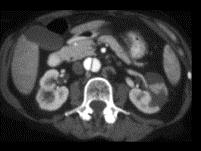

男,54岁,请根据所示图像,选择最可能诊断 ( )A、左侧肾梗死B、主动脉夹层C、左侧肾囊肿D、左侧肾积水E、左侧肾脓肿

问题 男,54岁,请根据所示图像,选择最可能诊断 ( )

选项 A、左侧肾梗死 B、主动脉夹层 C、左侧肾囊肿 D、左侧肾积水 E、左侧肾脓肿

答案 AB